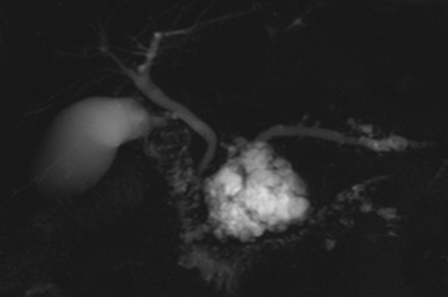

- On voit rarement la degenerescence dans la grappe elle meme de facon claire, ca fait des tumeurs infiltrantes , important de regarder les effets INDIRECTS (dilatation Wirsung, espaces péri-pancréatiques)

TIPMP des canaux secondaires

- Grappe vs lésion unique

- Communication avec Wirsung = clé